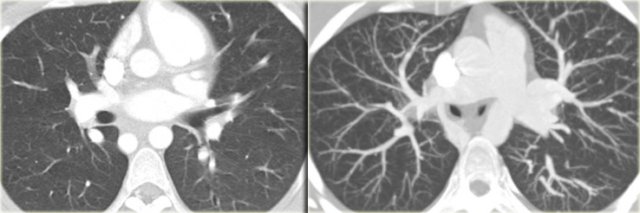

Right lower lobe anomalous return

On the left a right lower lobe anomalous return.

The vein drains into the IVC.

The anomalous vein gently curves to the right cardiophrenic angle and is shaped like a Turkish sword ('Scimitar')

Right lower lobe anomalous venous return into the azygos vein. Right lower lobe anomalous venous return into the azygos vein.

On the left another right lower lobe anomalous return.

The vein drains into the azygos vein.

Upper lobe veins may also drain into the azygos vein.

On the left a 10 year old girl suspected of having pneumonia.

Study the images carefully, because there are three findings and then continue reading.

The findings are:

• Small right lung due to hypoplasia

• Anomalous venous return

• Right aortic arch

This patient has a scimitar syndrome and also a right arch.

So the lesson is, that when you see one anomaly, look for another one.